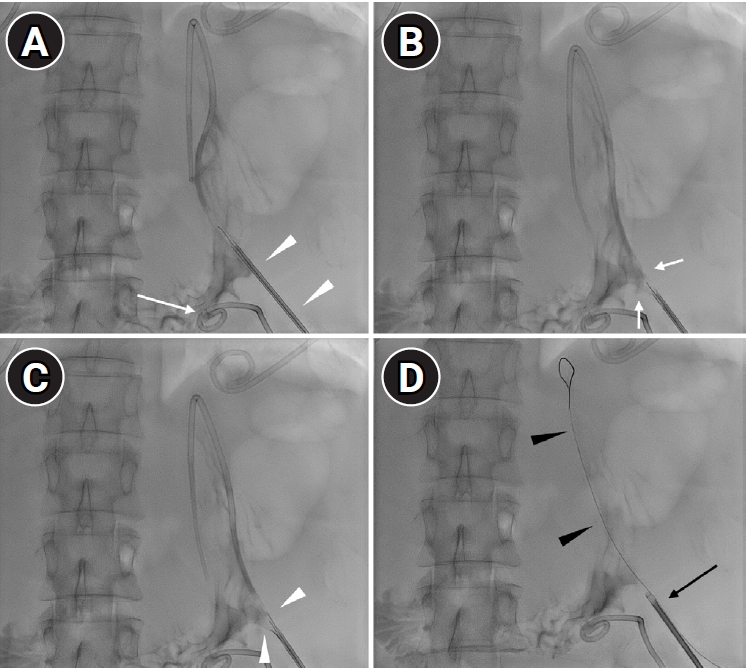

The cause of malposition was not clear, however, it may have been related to inadvertent advancement of the micropuncture needle or misinterpretation of ultrasonographic findings between the gas-filled stomach and the abscess. A wide space between the stomach and peritoneal wall, along with malnutrition due to prolonged fasting, may hinder normal tract maturation. In addition, instability caused by peristalsis and the lack of an anchoring system–unlike feeding gastrostomy–may further delay tract formation, necessitating safe closure of the perforation. After multidisciplinary discussion, safe retrieval of the PCD catheter was planned using a SMVCD instead of surgical treatment, as the patient had severe radiation-associated fibrosis from prior oncologic treatment. The catheter was exchanged over a 0.035-inch guidewire, and the SMVCD was advanced along the wire (

Fig. 2A). The foot was deployed and slightly retracted to achieve secure attachment under fluoroscopic guidance (

Fig. 2B). The needles pierced through the gastric wall by pushing the plunger and were then retracted (

Fig. 2C), and the puncture site was cinched using the suture trimmer (

Fig. 2D).

Fig. 2.Closing procedure. (A) An additional catheter was placed for perigastric fluid drainage (arrow). The misplaced drainage catheter was exchanged over 0.035-inch guidewire, and a suture-mediated vascular closing device was advanced along the guidewire (arrowheads). (B) The device foot was deployed and slightly retracted to create tenting of the gastric wall (arrows). Because the foot is radiolucent, proper placement was confirmed by gastric wall configuration. (C) The needles (arrowheads) penetrated the gastric wall upon pushing the plunger. (D) The suture was cinched using the trimmer (black arrow). A 0.018-inch guidewire (black arrowheads) was placed before removal of the SMVCD to allow a second attempt in case of failure.